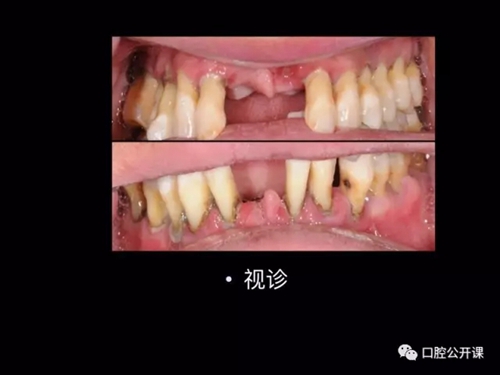

一例廣泛型侵襲性牙周炎5年臨床追蹤下

楊淑銀醫(yī)師用他的一例侵襲性牙周炎五年臨床病例追蹤來縮影一個青年牙周醫(yī)師的成長之路,帶我們一起探索看似平凡枯燥的牙周基礎治療到底有怎樣的重要性?